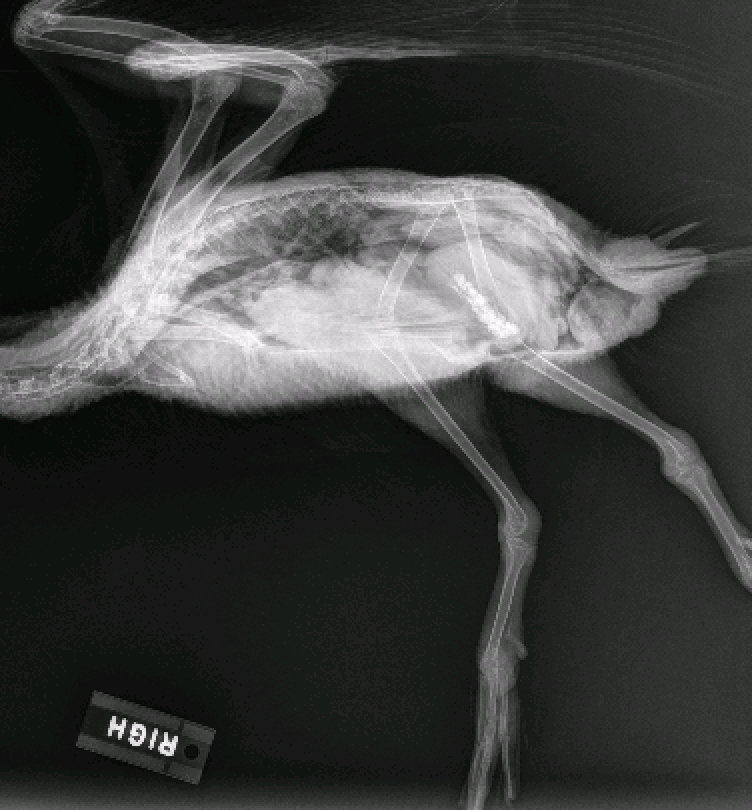

Since the patient was still having trouble walking and there was concern about the lesions on her feet, a plan was made to take radiographs. The patient was sedated and put under anesthesia to take the radiographs, which showed evidence of hind-end trauma. The pelvis appeared to have several fractures but in non-weight bearing portions and therefore was not a cause for concern. There was also an abnormality in the synsacrum, a fusion of the spine and pelvis found in avian species, which could beĀ causing inflammation and spinal problems. However, the issues noted on the radiographs did not seem to be recent, and the plan was to continue treatment with anti-inflammatory medication and provide increased swim time while monitoring for signs of improvement.